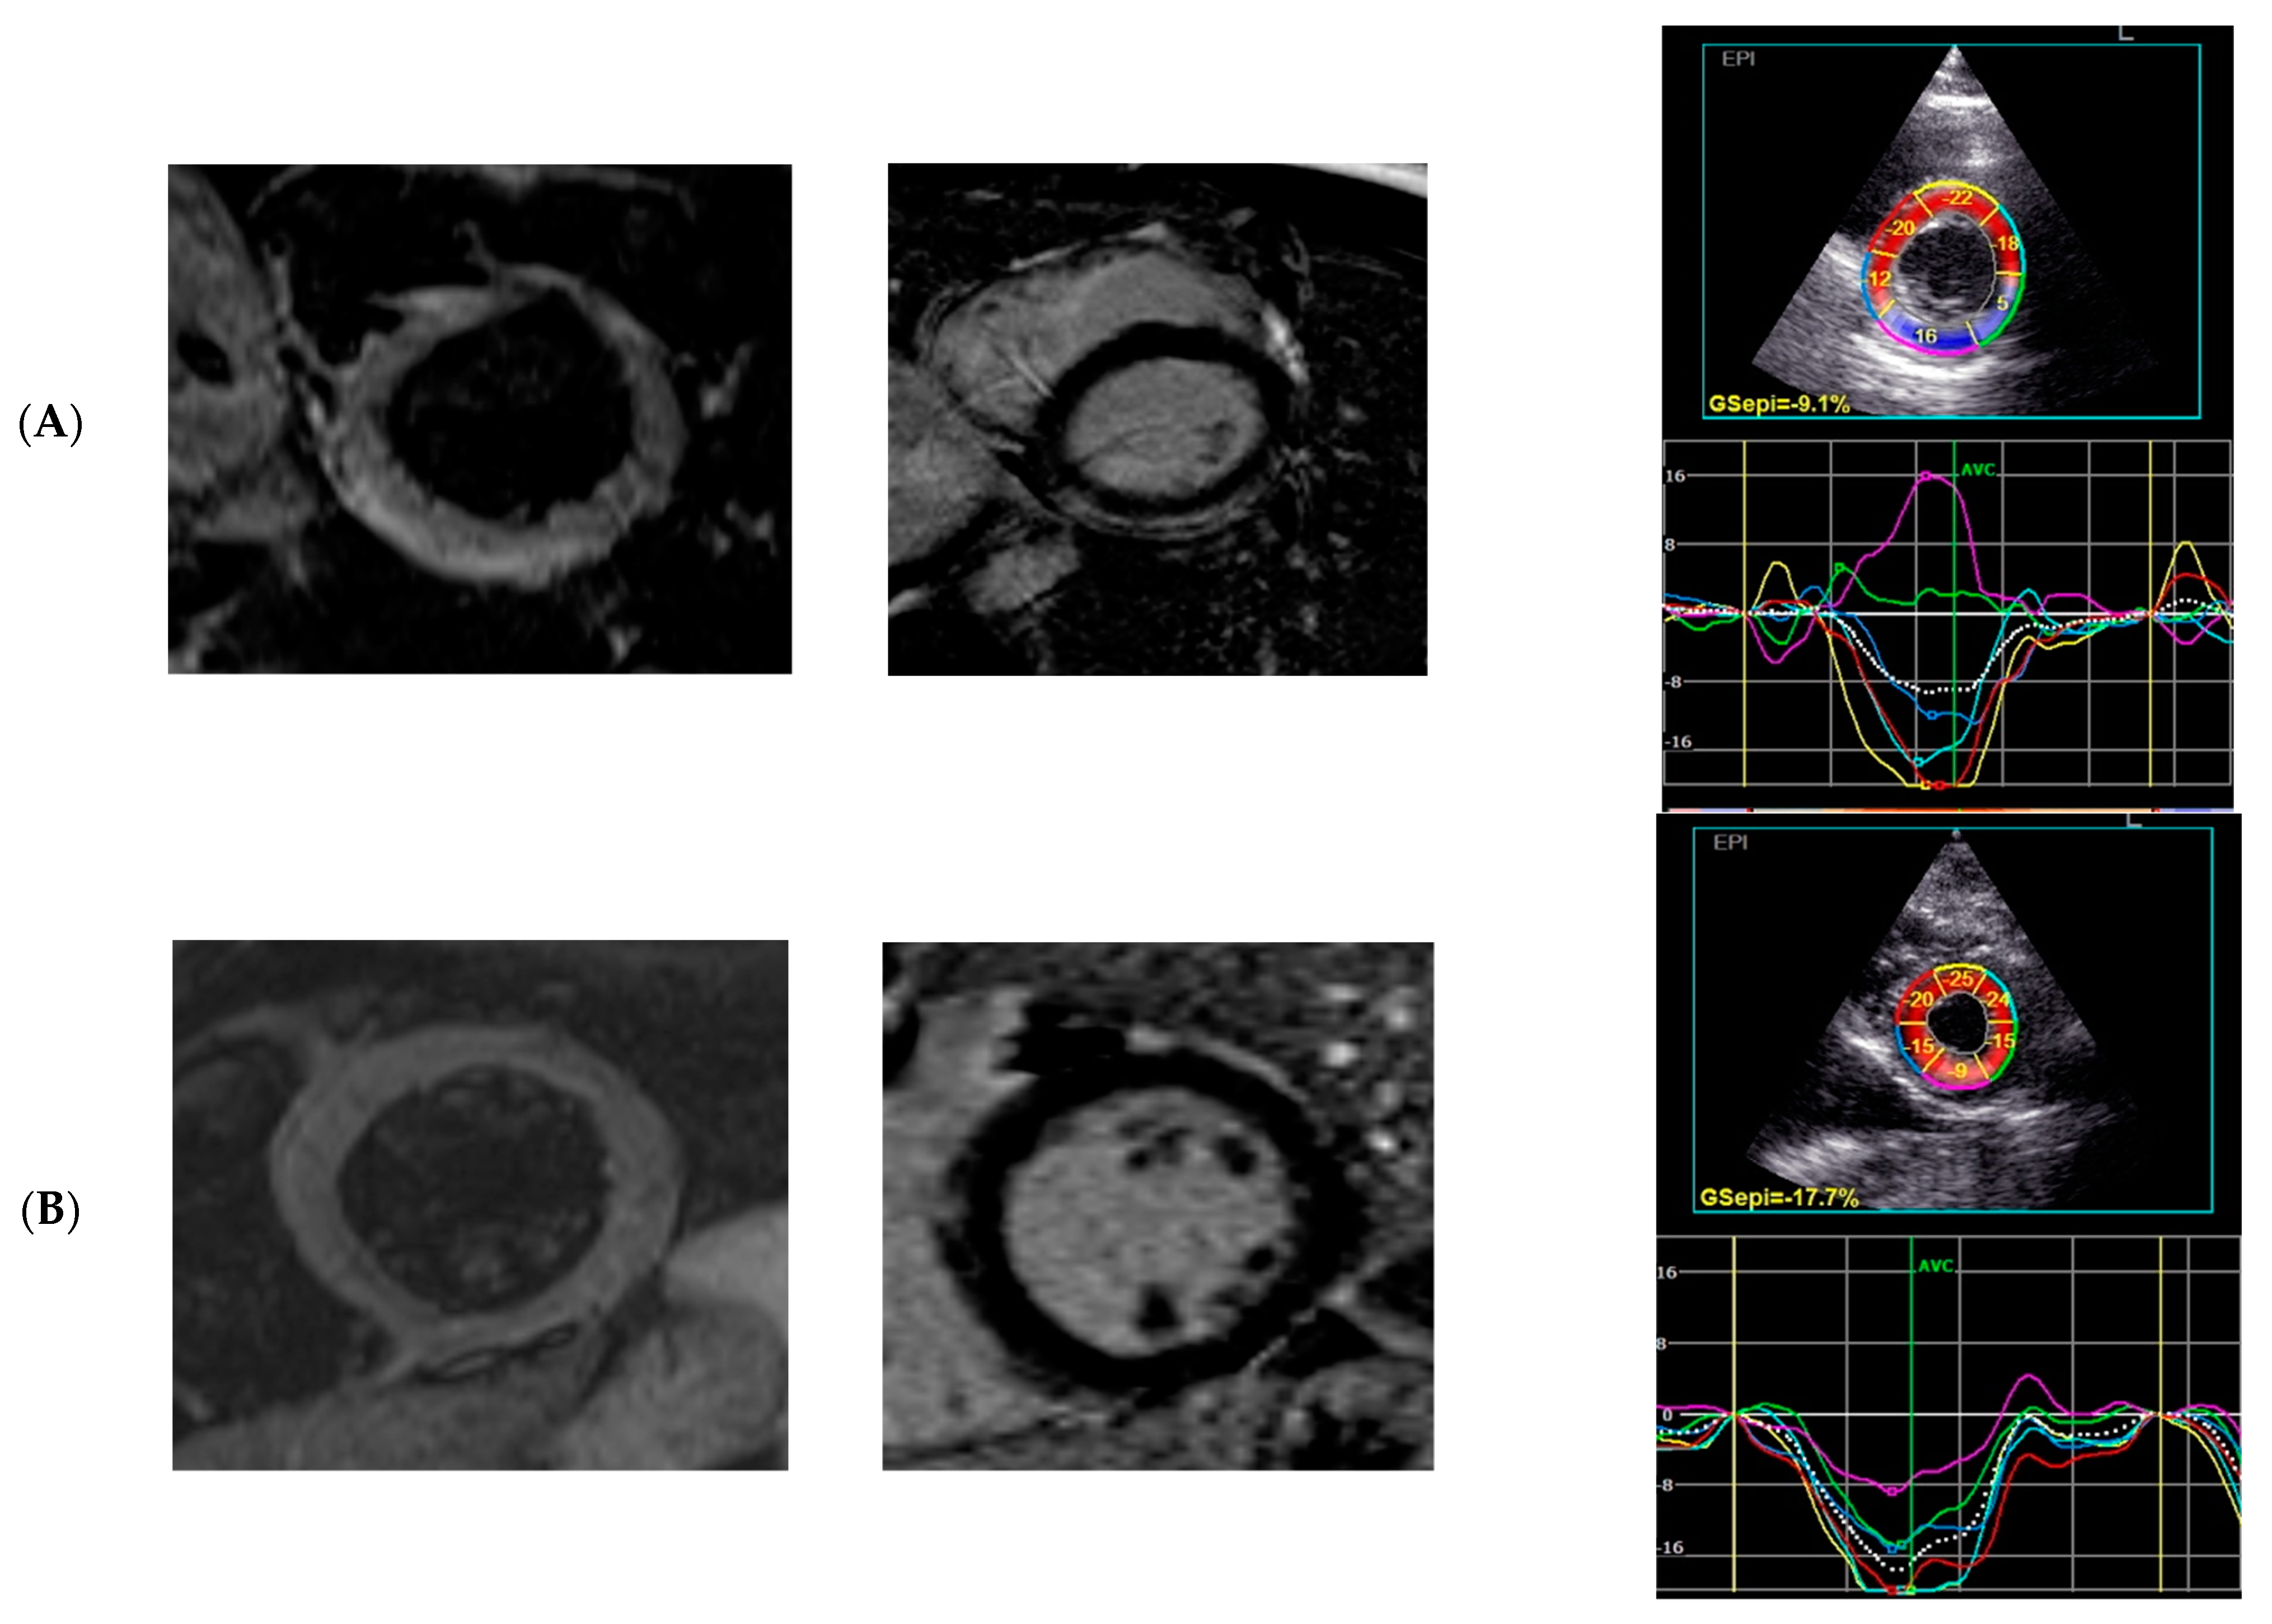

| GCS, % | −17.9 (−20.1–−15.3) | −16.8 (−18.4–−14.5) | −20.0 (−25.3–−17.3) | 0.001 |

| GCS MID systolic strain | −17 (−14.4–−19.4) | −15.7 (−17.2–−13.7) | −19.6 (−23.8–−16.6) | 0.000 |

| GCS EPI systolic strain | −10.6 (−13.5–−8.9) | −9.5 (−12.0–−7.5) | −12.7 (−15.9–−10.0) | 0.003 |

| GCS ENDO systolic strain | −26.2 (−29.8–−22.4) | −24.8 (−26.2–−20.8) | −28.8 (−35.8–−25.8) | 0.001 |